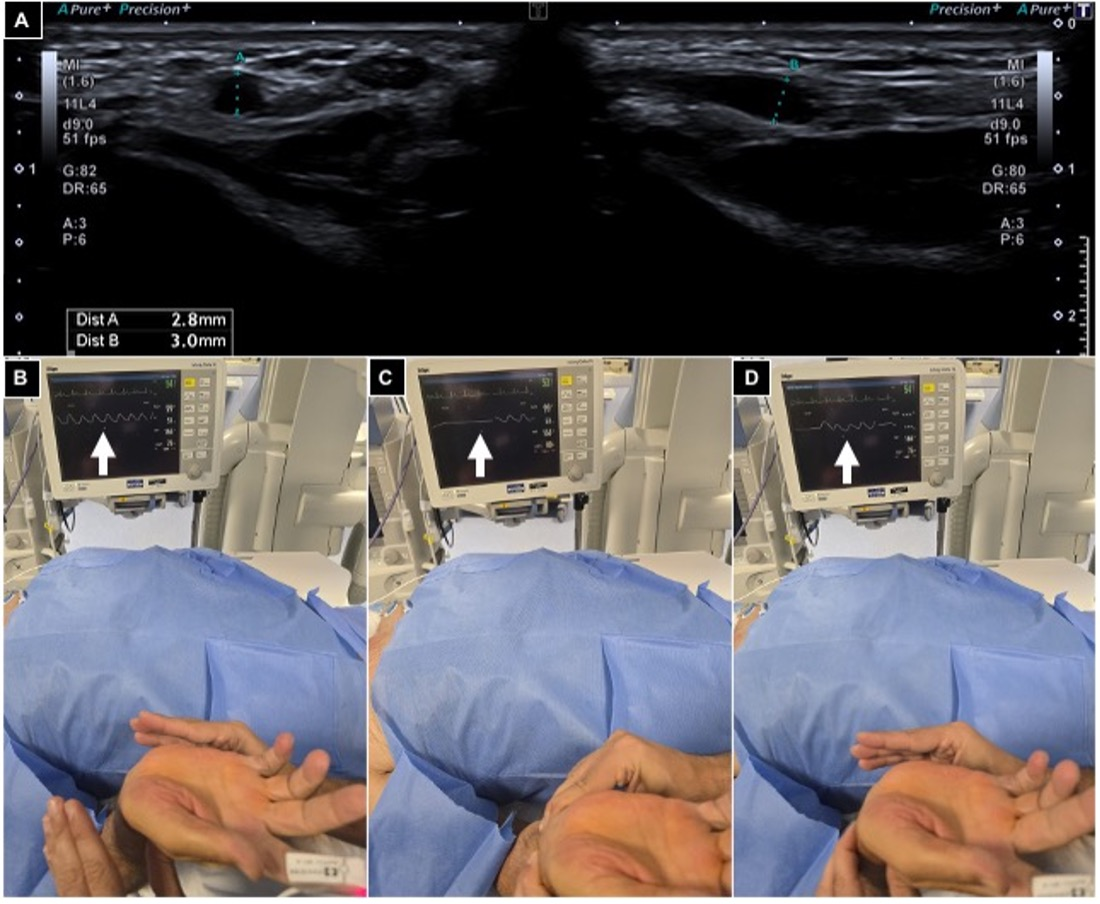

2.4. Procedures

- Aldin, Z.; Weaver, J.; Khan, M.; Sadik, T.; Manolas, V.; Tsampoukas, G.; Khatri, T.; Rebek, M.; Gharib, A.; Diss, J. A modified technique for radial artery access: How interventional radiologists can optimise the cardiologists’ technique to suite their procedures. CVIR Endovasc. 2025, 8, 1. [Google Scholar] [CrossRef] [PubMed]

- Gayed, A.; Yamada, R.; Bhatia, S.; Fischman, A.; Heran, M.K.S.; Himes, E.A.; Klass, D.; Patel, S.; Schiro, B.J.; Walker, T.G.; et al. Society of interventional radiology quality improvement standards on radial artery access. J. Vasc. Interv. Radiol. 2021, 32, 761.e1–761.e21. [Google Scholar] [CrossRef]